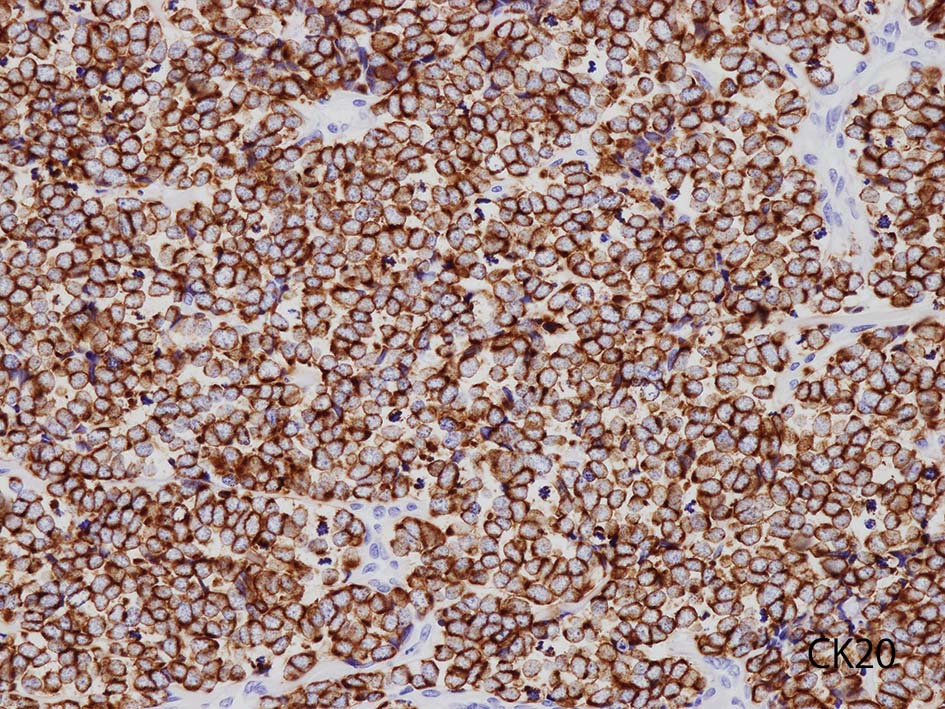

- 陽性上皮系マーカ; CAM5.2, AE1/3, CK20, BerEP4, EMA

- CK20の染色態度は核周囲にdot状にそまることが特徴的. (MCC[87%]のみではなく肺小細胞癌の4.6%にもこの陽性パターンをみることに注意*2)

CK20

血管を間質にしてround cellsが索状に増殖する所見. rossett様配列がある. CK20は特徴的な dot-like patternを示す. クリックで大きな画像が見られます.

本例では, dot状だけでなく, 細胞周囲にも陽性像が認められる.

CK(AE1/3); CK20は含まない, のほうがdot-likeな染まりをしている. CK20は膜にも陽性になっている. LCAは陰性. 神経内分泌マーカのchromograninA, synaptophysinは陽性.